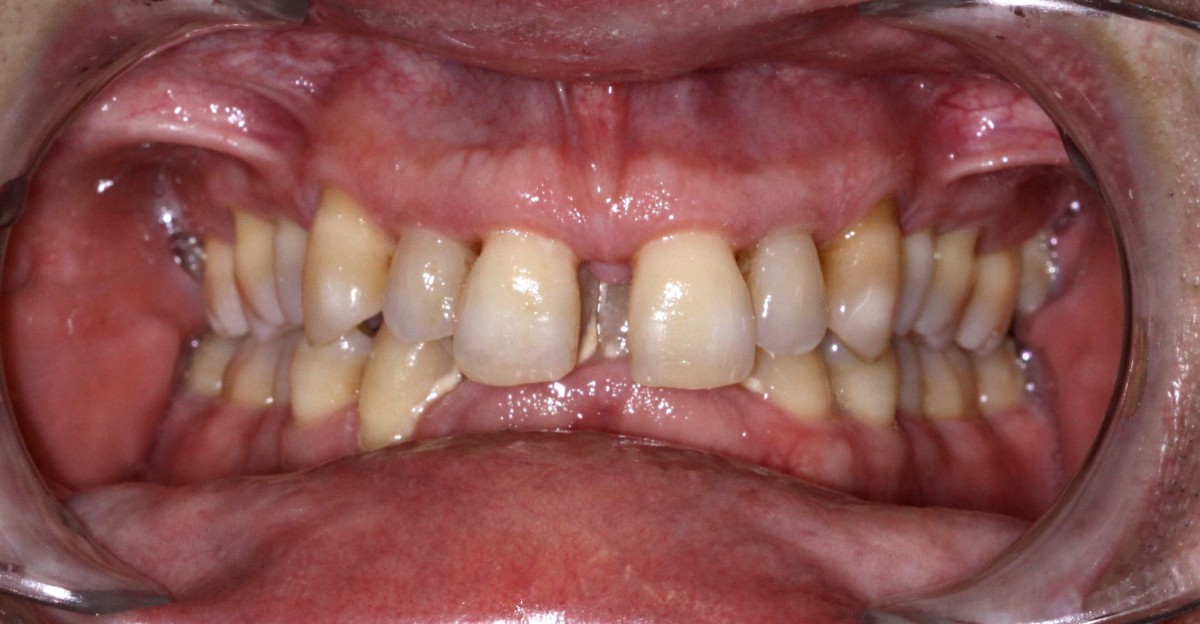

It is not every case that we con- sider a “life change”... this treatment for this patient was so important and the change we have achieved in his smile, function and aesthetics is dra- matic not to speak on the fact that we have probably saved his teeth from further destraction (figs. 12-16).

All treatments’ goals were achieved in very short time and with maximum aesthetics during the treatment with his clear aligners providing him perfect cleaning access with predictable and accurate technology. Patient received fixed retain- ers for anterior teeth and re- movable clear aligners for night wear (figs. 17, 18).